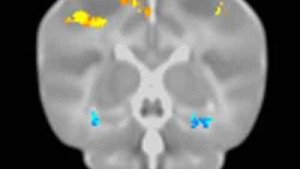

Un nuovo promettente composto ha mostrato di recuperare la memoria perduta e invertire i sintomi dell’Alzheimer.alzheimer La ricerca pubblicata dalla rivista FASEB Journal e’ opera dei National Institutes of Health. La molecola si chiama TFP5 e agisce sulle placche e sui accumuli caratteristici di questa malattia neurodegenerativa bloccando un segnale cerebrale che e’ iperattivo.Questo processo e’ riuscito a ripristinare le memorie di alcuni modelli murini in cui e’ stato iniettato il composto e nei quali era stata indotta una malattia equivalente all’Alzheimer umano.

Inoltre, non si e’ presentato nessun effetto collaterale. La molecola e’ stata introdotta con soluzione salina tramite iniezioni intraperitoneale mostrando una sostanziale riduzione dei vari sintomi della malattia con recupero della memoria perduta. Non si e’ poi presentata nessuna perdita di peso, stress neurologico o alcun segno di tossicita’. La TFP5 e’ stata ricavata da un enzima regolatore chiave del cervello, chiamato Cdk5: una attivita’ eccessiva di questo enzima e’ implicata nella formazione delle placche tipiche dell’Alzheimer.